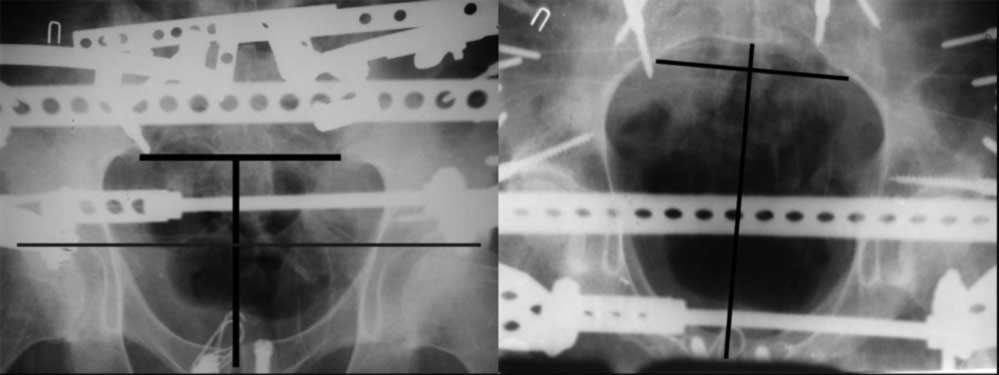

23.09.2003. Одновременный остеосинтез переднего и заднего тазовых полуколец

Результат через 10 дней

Это наблюдение 5-летней давности тогда кровопотеря составила 2,5 литра. В настоящий момент мы теряем не более 0,7-1,5 литров при одностороннем повреждении и около 2,5-3 литров тогда, когда речь идет о двусторонних повреждениях. Клинический пример.